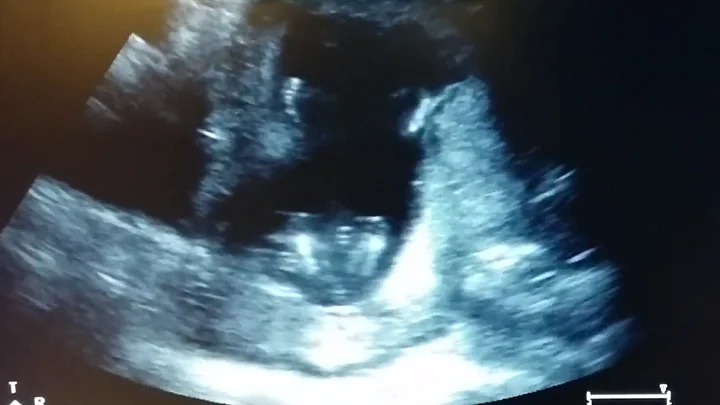

Reddit user Fishtails and his wife were surprised when their unborn baby started clapping during their 14 week ultrasound.

Unborn babies usually start movements around 25 weeks, so this little one in the ultrasound surely is an early bird!